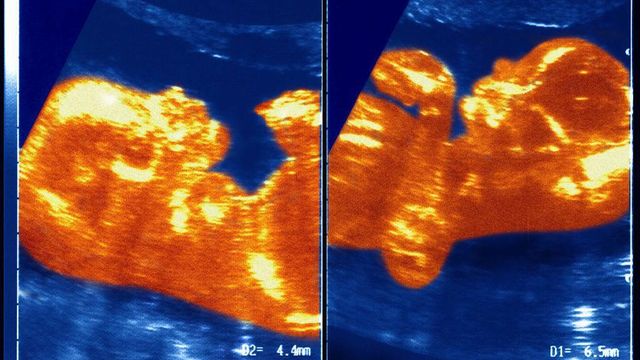

쌍둥이의 초음파 사진

이란성 쌍둥이는 서로의 DNA를 약 50% 정도만 공유하기에 일반적인 형제자매와 마찬가지로 유전적으로 서로 크게 다르다

연구진은 태아 시절 마르틴스의 태반과 쌍둥이 남자형제의 태반이 접촉하면서 혈관이 연결되었고, 이로 인해 남아의 혈액이 여아에게 전달된 것으로 추정한다.

마시엘 교수는 "우리가 '쌍둥이 수혈 증후군'이라 부르는 혈액 이동이 발생한 것"이라면서 여아와 남아의 동맹과 정맥이 탯줄 안에서 얽히면서 남아는 자신의 혈액 성분을 여아에게 전달하게 되었다고 설명했다.